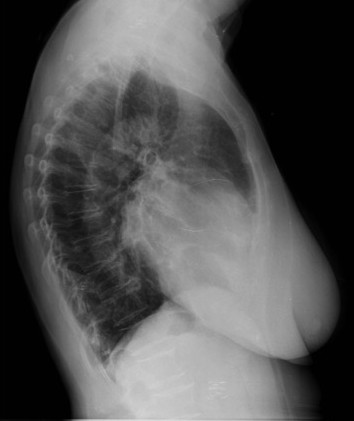

Solución: Es un estudio Normal. Silueta cardiomediastínica y parénquimas pulmonares sin alteraciones significativas.

En esta sección nos dedicaremos a la radiografía simple del Tórax. Iremos introduciendo casos de manera periódica con diversa semiología, así el objetivo es día a día quedarnos con un concepto radiológico fundamental, que luego nos sea de ayuda en nuestra práctica clínica rutinaria.

- Comprobar que la placa está bien centrada e inspirada (6 arcos costales anteriores ó 9 posteriores).

- Abdomen y Diafragma

- Partes blandas y estructura ósea.

- Mediastino con silueta cardiaca.

- Parénquimas pulmonares (por separado)

- Comparar un pulmón con otro.

Seguir esta sistemática, dejando el pulmón para el final no nos olvidaremos de lo más importante.

Regla: Acaso Tiene Mucha Patología Pulmonar (Abdomen, Tejidos blandos y hueso, Mediastino, Pulmón por separado, Pulmón bilateral)

Nota: ¡¡¡No olvidar la placa lateral!!! La regla a seguir es la misma. Leer abdomen y diafragma, examinar parte posterior, tejidos blandos y subir por la columna; tráquea y descender por mediastino. Finalmente pulmones.